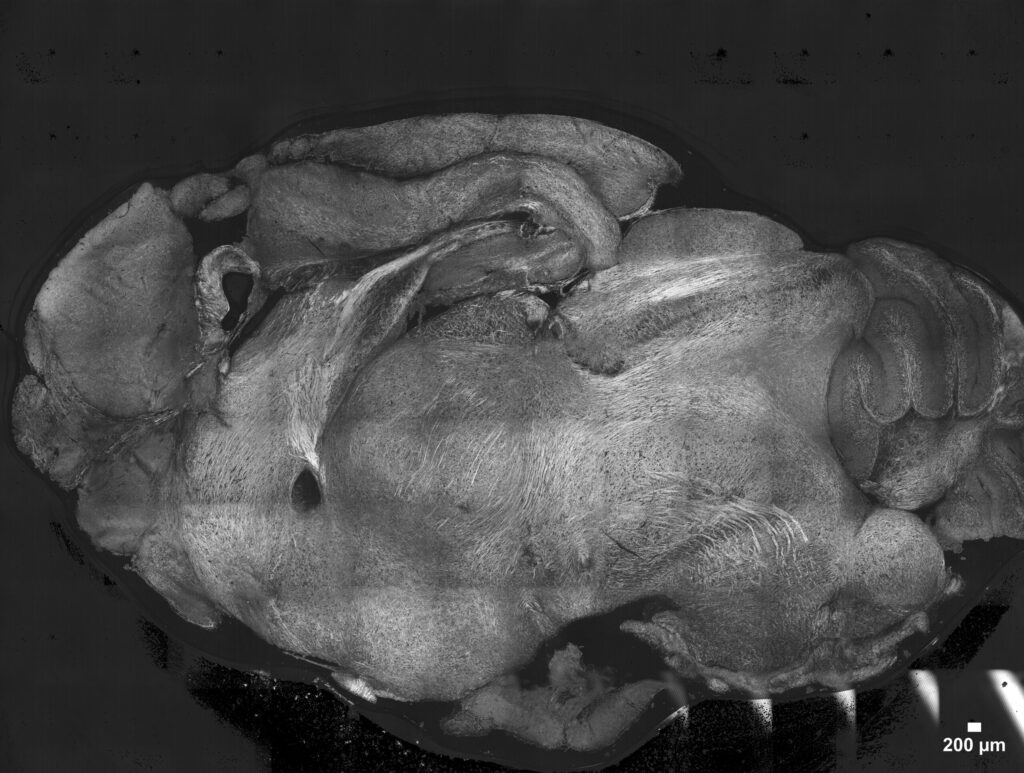

A recent research project led by Margaux Delaporte, Céline Raguénès-Nicol and Michel Samson (collaboration between Irset Institute and H2P2 platform) has introduced a new imaging protocol to explore the immune microenvironment of human hepatocellular carcinoma using multiplex immunofluorescence. Let’s take a closer look!

Understanding tumor heterogeneity through the immune microenvironment

Hepatocellular carcinoma (HCC) is characterized by pronounced intra- and inter-tumor heterogeneity, which represents a major challenge for the development and efficacy of targeted therapies. The immune microenvironment plays a central role in disease pathogenesis and in the response to treatment. Gaining a better understanding of this complexity requires approaches that can identify immune cell populations, their functional states, and their spatial organization within tumor tissue.

A multiplex immunofluorescence strategy based on Cell DIVE

In this study, Delaporte et al.1 present a multiplex immunofluorescence (mIF) protocol based on the Cell DIVE technology, enabling the simultaneous detection of multiple protein markers on a single section of human hepatocellular carcinoma. The aim of this approach is to perform detailed immunophenotyping of the tumor microenvironment while preserving tissue architecture.

Cell DIVE relies on successive cycles of immunofluorescent staining, high-resolution image acquisition, and chemical inactivation of fluorochromes. Images from each cycle are aligned using nuclear DAPI staining as a common reference and assembled to generate a final multiparametric image of the entire tissue section. Image analysis is performed using open-source tools, notably QuPath, for cell segmentation and phenotyping.

Schematic summary of the workflow for tissue processing, antibody preparation, image acquisition, and treatment

A multiparametric view of the tumor immune ecosystem

The protocol is based on a 20-marker panel combining cellular positioning markers, structural markers of normal and pathological liver tissue, vascular markers, and markers identifying major myeloid and lymphoid populations. Markers of lymphocyte activation, exhaustion, and immune checkpoints are also included to explore the functional status of immune cells within the tumor microenvironment.

This approach enables the generation of a multiparametric, single-cell-resolution spatial map of the immune microenvironment in HCC from a single histological section. It allows the spatial distribution of immune cells and their relationships with tumor and vascular structures to be investigated, while remaining compatible with human samples commonly available in translational and clinical research. The authors also indicate that the methodology can be applied to the study of liver immune infiltration in other pathological contexts and adapted to tissues beyond the liver.

Example of final mIF image of human hepatocellular carcinoma whole slide. For visualization purposes, only 5 markers are displayed: WGA (yellow), CD4 (orange), CD20 (green), CD31 (red), CD68 (blue) and DAPI (gray). Scale bar represents 2 mm.

Technical constraints and practical considerations

The main limitation of this protocol is the requirement for access to a Cell DIVE imaging system, which is essential for multiplex image acquisition. The repetition of staining cycles may also pose challenges for fragile tissues, as tissue detachment can compromise image alignment. In addition, the cell segmentation approaches used are primarily optimized for nuclei and may be less suitable for cells with complex or non-rounded morphologies.

Expanding the applications of multiplex spatial imaging

Overall, this protocol highlights the potential of multiplex imaging technologies to overcome the limitations of conventional histology. By combining immunophenotyping with spatial information at single-cell resolution, it provides a powerful framework for studying the immune microenvironment of hepatocellular carcinoma and contributes to a deeper understanding of tumor heterogeneity in human tissues.